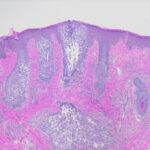

Follicular Mucinosis = الداء المخاطيني الجرابي

Mucinoses There are six types of cutaneous mucinosis: (a) generalized myxedema, (b) pretibial myxedema, (c) lichen myxedematosus or papular mucinosis, (d) reticular erythematous mucinosis or plaquelike mucinosis, (e) selfhealing juvenile cutaneous mucinosis, and (f) scleredema. |